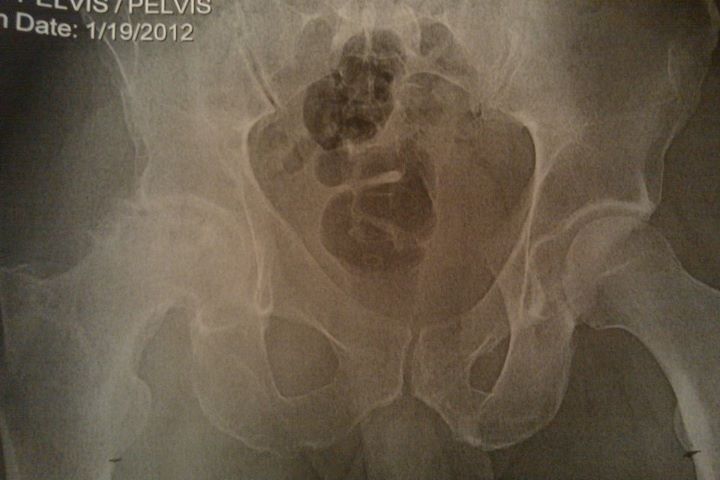

Good thoughts welcome....DH is going in for his hip replacement this afternoon. He's only 38, but has severe degeneration of the joint - the xrays are pretty ugly, and the doctor was surprised he can walk, let alone climb trees every day (he's a line clearance tree trimmer). Luckily, it's only his one hip, the other is in good shape. He'll be off work for up to 3 months (due to his work, he can't go back until he's 100% healed, no "easy" jobs for him to do, it's all go the day he goes back). He's hoping he can be ready to go in two months.